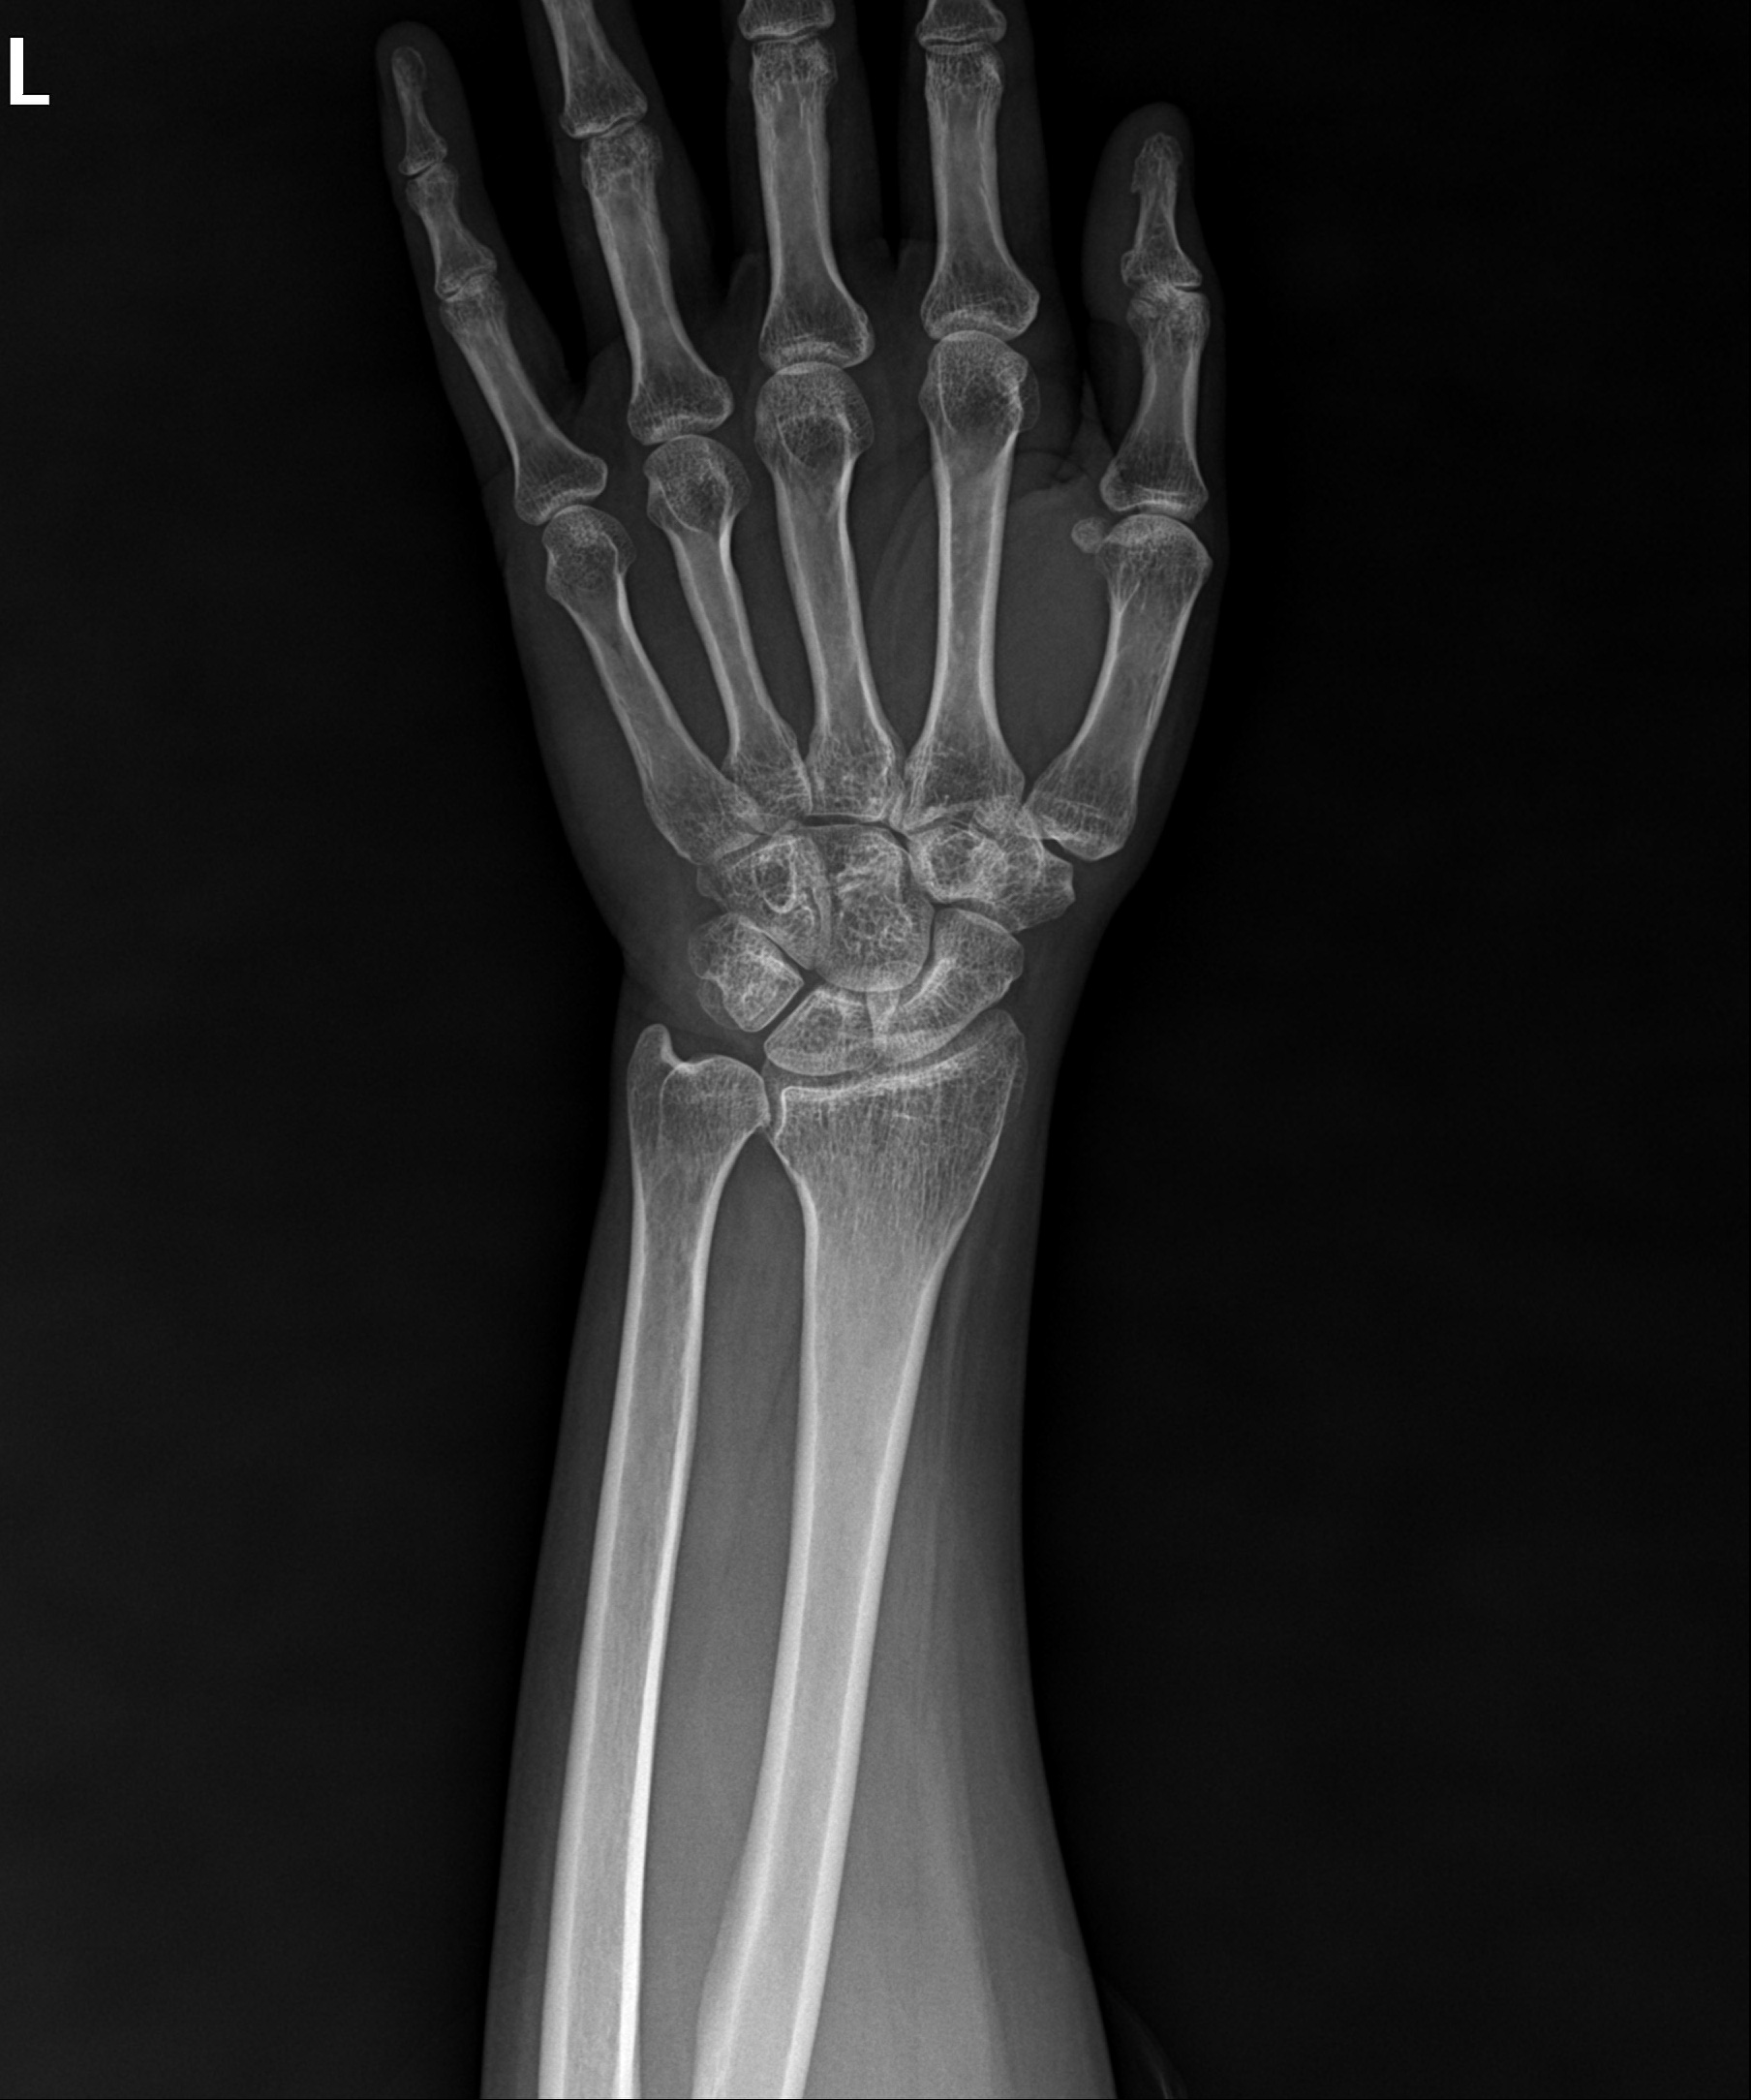

척골 단축술 후 고정된 모습

2022.12.05